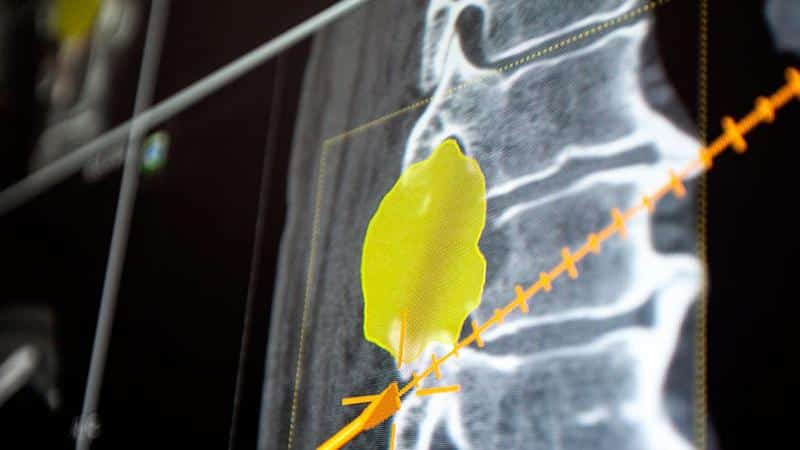

Для определения локализации заболевания применяется рентгенодиагностика, однако ее точность значительно ниже, чем у компьютерной или магнитно-резонансной томографии. Поэтому предпочтительнее использовать именно эти методы. В некоторых случаях может понадобиться ультразвуковое исследование, чтобы оценить состояние окружающих мягких тканей.

Кроме того, необходимо провести биопсию опухоли, так как это позволяет получить информацию о том, является ли процесс злокачественным или доброкачественным, и помогает выбрать правильную стратегию лечения.